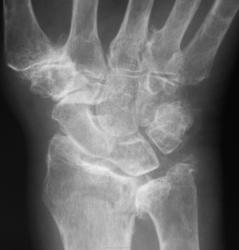

Травма. Пациент направлен на рентгенографию лучезапястного сустава.